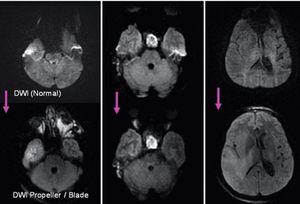

Due to susceptibility issues SS-EPI DWI in specific body parts (e.g. skull base, IAC) used to be difficult. DWI Propeller provides significantly increased image quality in the area of interest with reduced image distortions.